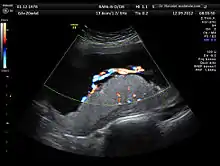

Anatomy scan image of a human placenta and umbilical cord (colour Doppler rendering) showing central placement of the cord in the placenta and three vessels in the cord, which is the normal physiology.